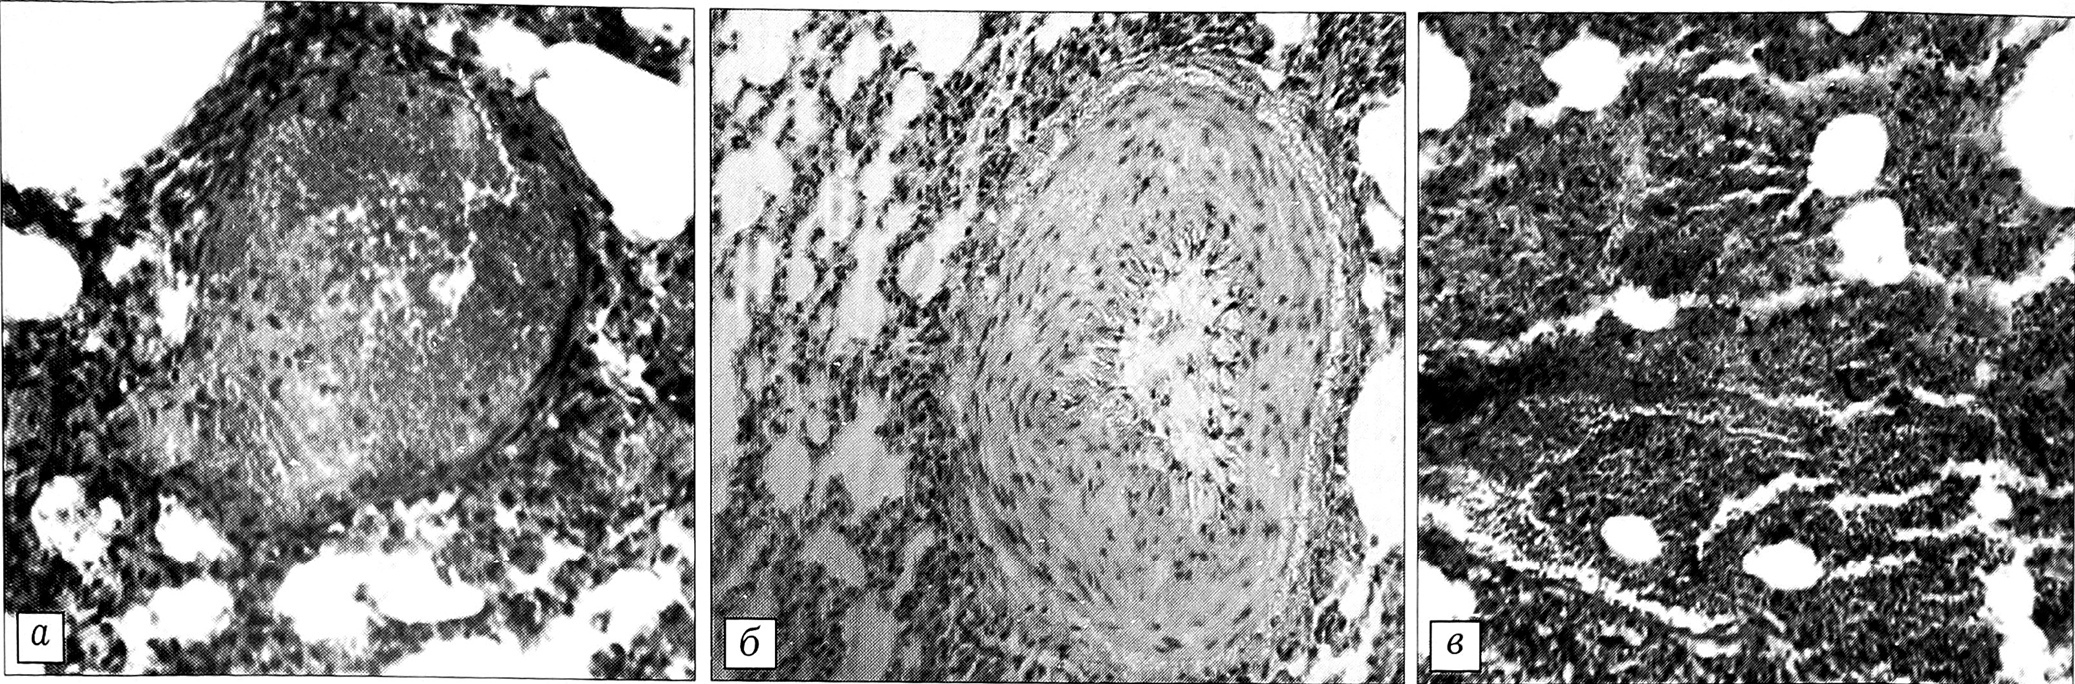

У животных контрольной группы наиболее выраженные изменения, заметные уже при макроскопическом исследовании, обнаружены в легких. Отмечалось неравномерное синюшно-красное окрашивание висцеральной плевры и снижение воздушности легочной ткани. Микроскопически выявлялись расстройства кровообращения: полнокровие сосудов всех типов, обширные поля кровоизлияний с разрывами стенок капилляров (рис. 1,а) и межальвеолярных перегородок; в некоторых сосудах определялись очаги набухания и слущивания эндотелиоцитов (рис. 1, б). Сосуды межальвеолярных перегородок были неравномерно полнокровны, в части случаев эритроциты как вне, так и внутри сосудов имели нечеткие контуры, что свидетельствовало об их гемолизе. На значительных участках картина кровоизлияний напоминала геморрагический инфаркт легкого (рис. 1, в). Обращало на себя внимание преимущественно субплевральное расположение кровоизлияний. Кроме эритроцитов, в просвете альвеол на значительных участках наблюдалось скопление отечной жидкости. Выявлялись очажки спадания легочной ткани — дистелектазы. Изменений эпителия бронхов при этом не отмечено.

У животных основной группы, получавших протективные препараты, морфологическая картина легких отличалась от описанной выше. Макроскопически легкие не имели столь выраженной синюшной окраски, ткань их была болеее воздушной, что подтверждено микроскопически. У части животных кровоизлияния в просвет альвеол полностью отсутствовали, у остальных выявлялись небольшие очажки преимущественно субплевральных кровоизлияний. При этом в альвеолах не содержалось отечной жидкости, что указывало на сохранение целости альвеолярно-капиллярного барьера. В то же время у всех животных имели место дистелектазы и полнокровие сосудов межальвеолярных перегородок.

Рис. 1. Микроскопическая картина легкого кролика контрольной группы (окраска гематоксилином и эозином).а — разрыв стенки сосуда (ув. 240); б — спазм стенки артериолы, набухание и слущивание эндотелиоцитов (ув. 240); в — обширные кровоизлияния в паренхиму, напоминающие инфаркт легкого (ув. 140).